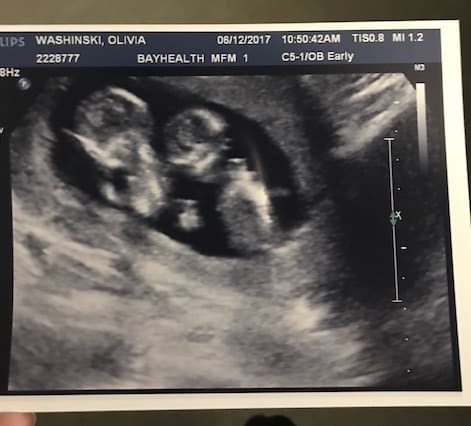

- Ultrasound Photos at 13 Weeks Pregnant With Twin

Ultrasound Photos at 13 Weeks Pregnant With Twin